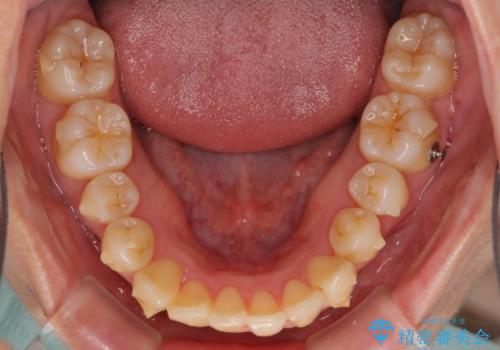

突出した印象のあった前歯をきれいに引っ込めることができたので、口が閉じやすくなり、横顔の印象をスッキリとさせることができました。

でこぼこしていて磨きにくかった歯と歯の間も清掃しやすくなり、患者様には大変満足していただきました。